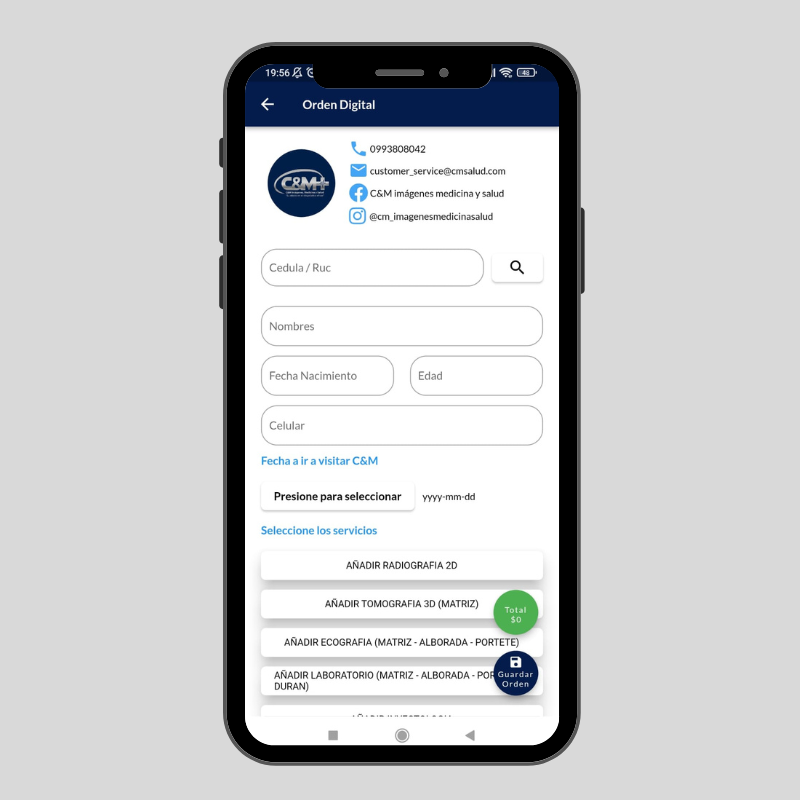

Tu tiempo es valioso imagenes, resultados y más directo a su teléfono y al de su doctor!

- Vamos de la mano con la tecnología